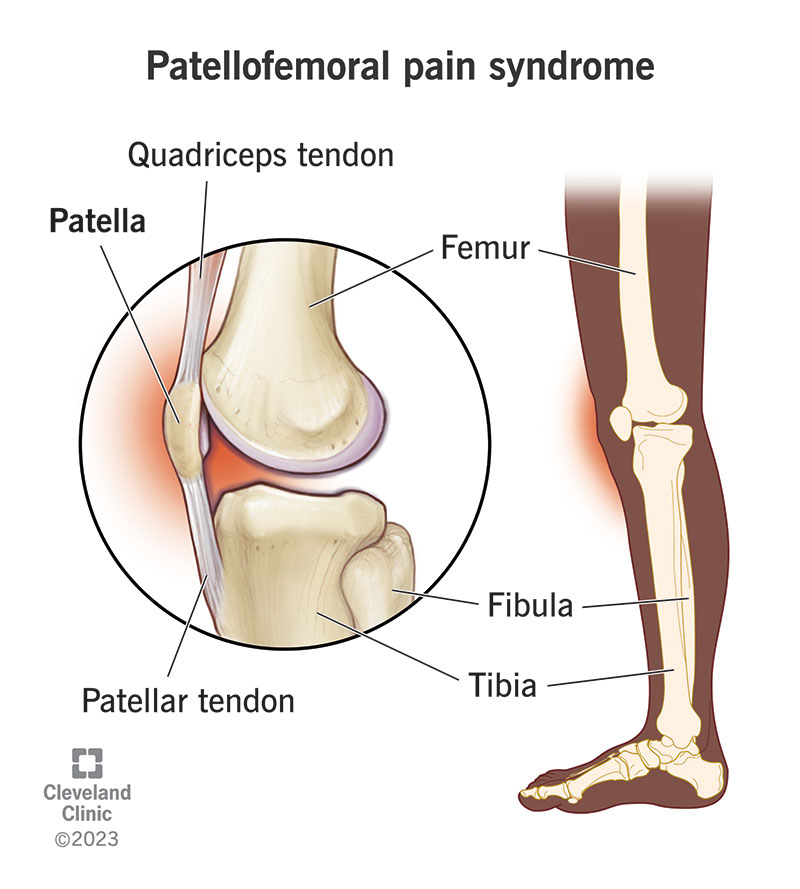

Where or Where Has My Patella Gone Direct Orthopedic Care 2024, Patella Kneecap Anatomy and Function 2024, Patellofemoral Pain Syndrome OrthoInfo AAOS 2024, The Patella Surface Anatomy Functions Dislocation 2024, Patella Wikipedia 2024, Patellar Fractures Broken Kneecap OrthoInfo AAOS 2024, Patellofemoral Joint Structure Function Conditions 2024, Patellofemoral Joint Physiopedia 2024, Patellar region Flashcards Quizlet 2024, Patella Injury Treatments Knee Surgeons Consultants Yorkshire 2024, Patella Anatomy function and clinical aspects Kenhub 2024, Patellar Tendonitis Jumper s Knee Johns Hopkins Medicine 2024, ITB vs Patellofemoral Pain Syndrome Symptoms Knee Pain In Runners 2024, Patellofemoral Pain Syndrome OrthoInfo AAOS 2024, Patella Anatomy function and clinical aspects Kenhub 2024, Patellar Tendonitis Jumpers Knee Symptoms Diagnosis Treatment 2024, Patellofemoral Pain Syndrome Rural Physio at Your Doorstep 2024, Patellar tendinitis Symptoms causes Mayo Clinic 2024, Patella Femoral Syndrome Montgomery Massage Therapy 2024, Jumper s Knee Symptoms in Kids Jumper s Knee Treatment 2024, Anatomy of Patella Bone and Spine 2024, Patellar Tendonitis Jumper s Knee Symptoms Causes Mount 2024, Anatomy Gruppo Bioimpianti 2024, Patellofemoral Pain Syndrome 2024, Patella Tendinopathy also known as Jumper s Knee Complete Physio 2024, Patellofemoral Pain Syndrome PFPS Symptoms Treatment 2024, Patellar Tendonitis 2024, Patellofemoral Joint Physiopedia 2024, How to avoid Runner s Knee . Forty two percent of all overuse 2024, Osgood Schlatter Disease Knee Pain OrthoInfo AAOS 2024, Tendinitis in the Knee 2024, Patella Kneecap Definition Location Anatomy Diagram 2024, Patellar Tendinopathy Rural Physio at Your Doorstep Physio Direct 2024, Knee Pain Location Chart SPORT Orthopedics Dallas and Frisco 2024, 10 Common Knee Injuries Diseases 2024.

Where or Where Has My Patella Gone Direct Orthopedic Care 2024, Patella Kneecap Anatomy and Function 2024, Patellofemoral Pain Syndrome OrthoInfo AAOS 2024, The Patella Surface Anatomy Functions Dislocation 2024, Patella Wikipedia 2024, Patellar Fractures Broken Kneecap OrthoInfo AAOS 2024, Patellofemoral Joint Structure Function Conditions 2024, Patellofemoral Joint Physiopedia 2024, Patellar region Flashcards Quizlet 2024, Patella Injury Treatments Knee Surgeons Consultants Yorkshire 2024, Patella Anatomy function and clinical aspects Kenhub 2024, Patellar Tendonitis Jumper s Knee Johns Hopkins Medicine 2024, ITB vs Patellofemoral Pain Syndrome Symptoms Knee Pain In Runners 2024, Patellofemoral Pain Syndrome OrthoInfo AAOS 2024, Patella Anatomy function and clinical aspects Kenhub 2024, Patellar Tendonitis Jumpers Knee Symptoms Diagnosis Treatment 2024, Patellofemoral Pain Syndrome Rural Physio at Your Doorstep 2024, Patellar tendinitis Symptoms causes Mayo Clinic 2024, Patella Femoral Syndrome Montgomery Massage Therapy 2024, Jumper s Knee Symptoms in Kids Jumper s Knee Treatment 2024, Anatomy of Patella Bone and Spine 2024, Patellar Tendonitis Jumper s Knee Symptoms Causes Mount 2024, Anatomy Gruppo Bioimpianti 2024, Patellofemoral Pain Syndrome 2024, Patella Tendinopathy also known as Jumper s Knee Complete Physio 2024, Patellofemoral Pain Syndrome PFPS Symptoms Treatment 2024, Patellar Tendonitis 2024, Patellofemoral Joint Physiopedia 2024, How to avoid Runner s Knee . Forty two percent of all overuse 2024, Osgood Schlatter Disease Knee Pain OrthoInfo AAOS 2024, Tendinitis in the Knee 2024, Patella Kneecap Definition Location Anatomy Diagram 2024, Patellar Tendinopathy Rural Physio at Your Doorstep Physio Direct 2024, Knee Pain Location Chart SPORT Orthopedics Dallas and Frisco 2024, 10 Common Knee Injuries Diseases 2024.